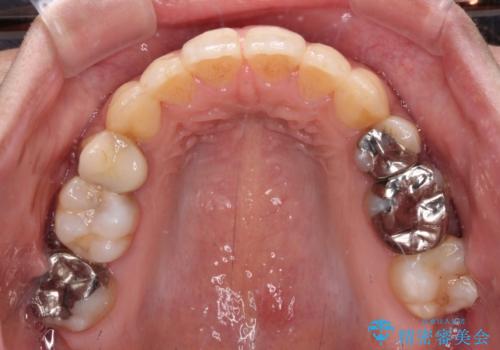

後戻りで突出した前歯をインビザラインで解消

- 抜歯矯正の後戻りで前歯が突出してきていることを気にして来院された患者様です。

口元の突出感を改善するにあたり、抜歯矯正は行うことができないため、奥歯の後方移動とIPR(歯と歯の間を削る)により達成することとしました。

再度後戻りしたときに対応しやすいよう、インビザラインにて矯正治療を行うこととしました。

舌の突出癖がなかなか改善できず、IPRによる前歯の隙間が閉じきらずに、予定よりも長い治療期間となりました。